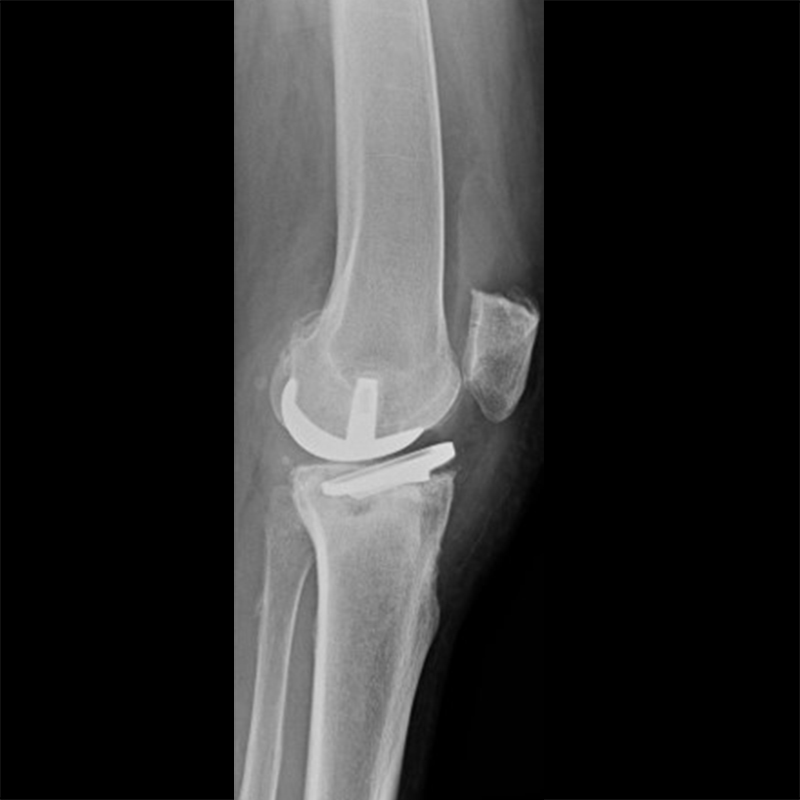

外院失敗本院再置換 首頁 案例分享 膝關節手術 外院失敗本院再置換 蕭女士 69歲 術前 術後 81歲 林女士 術前 術後 蕭女士 69歲 術前 術後 鄒女士 69歲 術前 術後 李女士 74歲 術前 術後 吳女士 71歲 術前 術後 謝女士 65歲 術前 術後